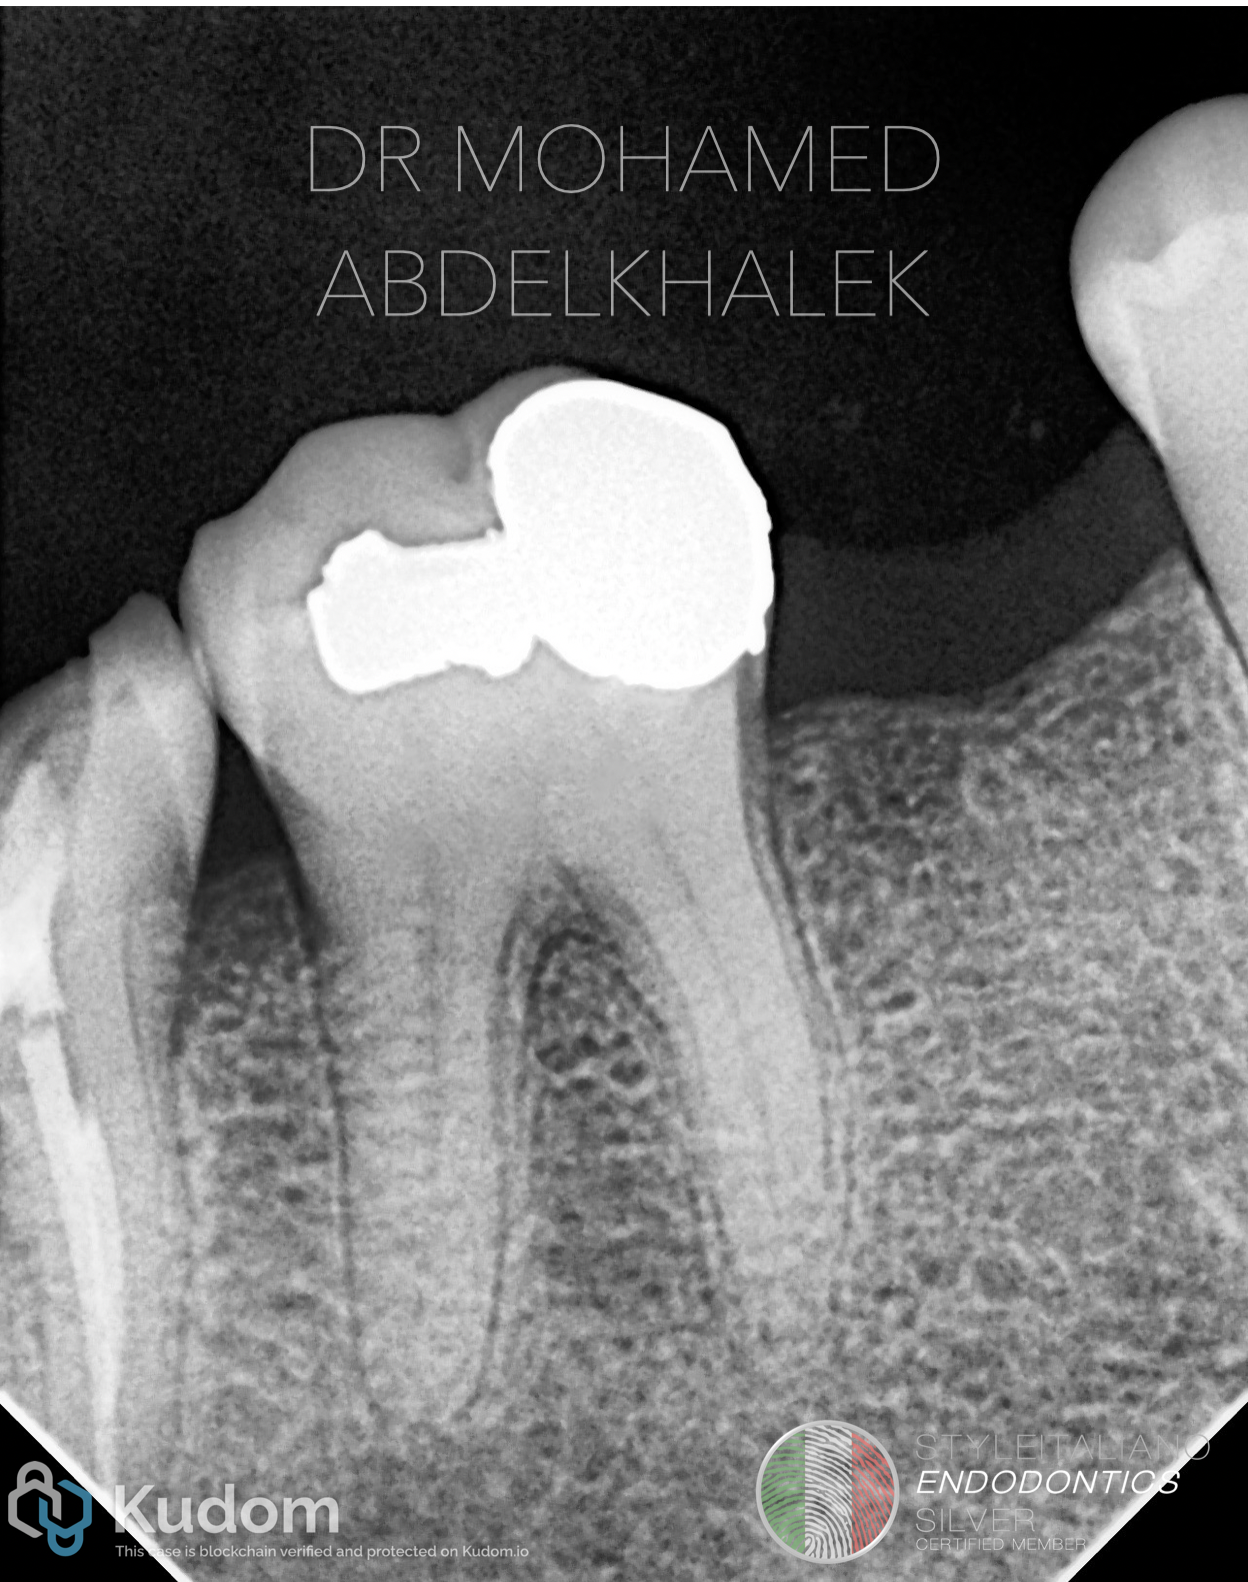

Mandibular first molars are particularly susceptible due to their early eruption time and prolonged exposure to irritants. Calcification may affect one or multiple canals, often leading to partial or complete obliteration.

Fig. 1